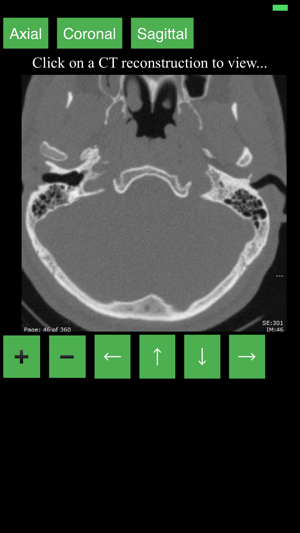

This app provides a dynamic and interactive method of viewing cross-sectional human anatomy on compu

This app provides a dynamic and interactive method of viewing cross-sectional human anatomy on compu